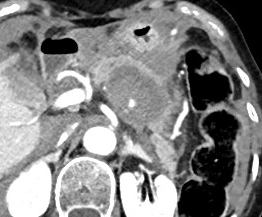

@dpduncanMD_IR @VUMCradiology @UCSDRadRes @Quinn_Meisinger @myliuMD @shelbyfrantzMD @iRadRock @MinaMakaryMD @theIIMD @IRdocAndy @JohnDoIR @RmelikMD @TWongMD @DRimaniIR @danbrownIO @ecemmons @CBoonie_nanoIR @Ajairam_MD_IR pubmed.ncbi.nlm.nih.gov/35907643/ I’ve always thought this was a great case. Great technique by the IR to boot!